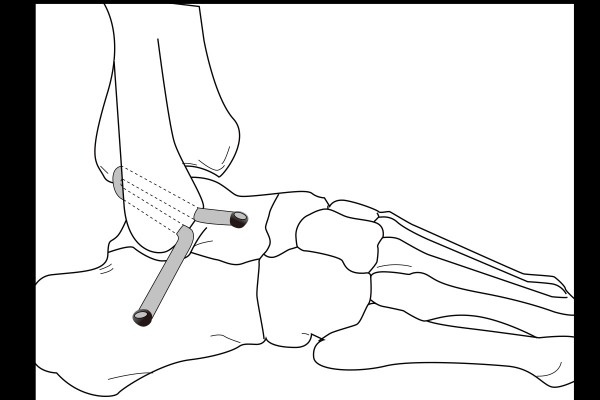

인대 재건,이식을 위하여 기존의 봉합을 위한 절개창 보다 작은 절개창 3개(최소절개)를 내어주고, 인대를 이식하여 재건해줍니다.

이해를 쉽게 하기 위해, 전거비인대와 종비인대가 재건된 모식도를 첨부합니다.